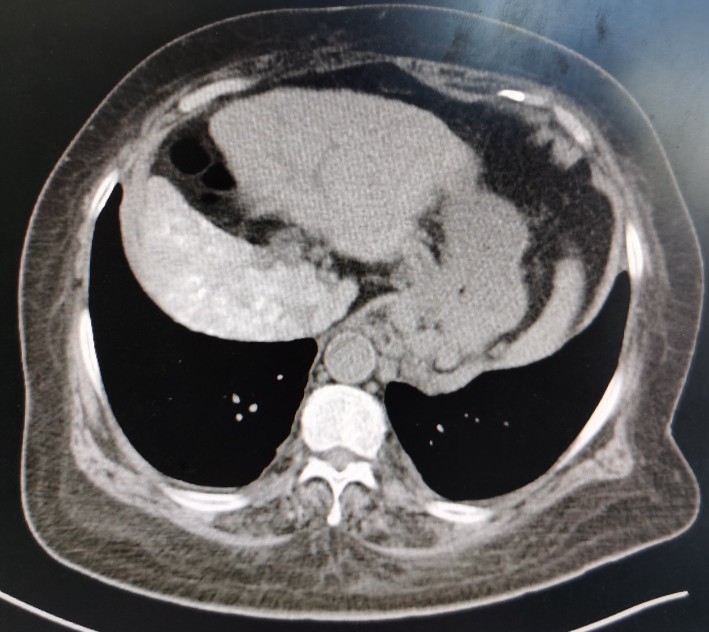

肝脏

正常肝脏CT片

黄婶的肝脏,左右分明,左右肝均萎缩,脾大

萎缩的右肝发展成了肝癌

肝癌向下生长